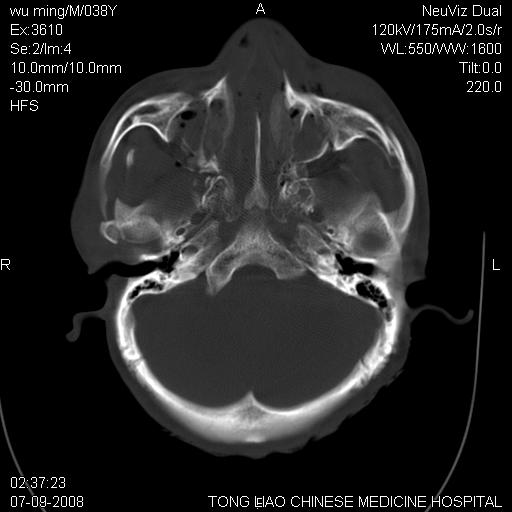

标题: CT14544:患者5楼坠下15分钟后CT扫描,2小时后死亡,请战友指 [打印本页]

标题: CT14544:患者5楼坠下15分钟后CT扫描,2小时后死亡,请战友指

颅底多发骨折。

颅底多发骨折.

颅底多发骨折.上颌骨多发骨折

考虑:面骨、颅底骨多发骨折,颅内高压(脑肿胀)。

1)颅底骨及颌面骨多发性骨折。2)副鼻窦及双侧鼻腔积血。

颅底骨折,窦腔内积血。考虑死亡原因为脑水肿压迫脑干或因大量失血死亡。

颅底、上颌骨,双侧颧骨多发骨折。死因或许与此无关,是否有腹部脏器损伤有关